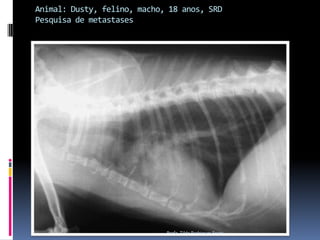

Animal: Dusty, felino, macho, 18 anos, SRDPesquisa de metastasesProfa. Tilde Rodrigues Froes

Animal: Dusty, felino,macho, 18 anos, SRDPesquisa de metastasesProfa. Tilde Rodrigues Froes